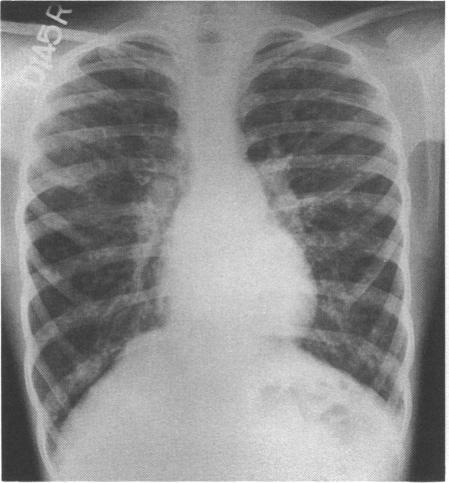

The chest radiograph in cystic fibrosis in children and the role of other radiological techniques.

J R Soc Med. 1987;80 Suppl 15(Suppl 15):38-46.

原文链接:https://pmc.ncbi.nlm.nih.gov/articles/PMC1290612/